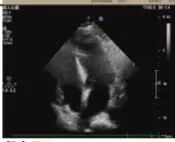

术后超声

病理诊断

术后病理显示,患者左房肿瘤为良性黏液瘤,完整切除后无需后续治疗。经过10天的康复治疗,老人顺利出院。这一案例中,多学科团队通过术前风险分层、术中精密协作、术后个体化护理,为高龄复杂心脏疾病患者的救治积累了临床经验